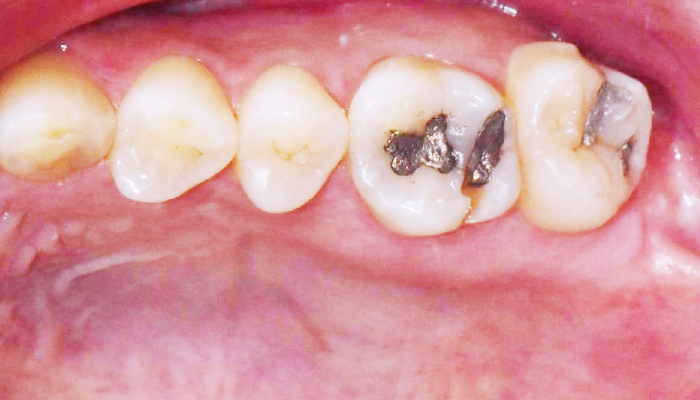

• 충치예방

정기적인 스케일링으로 충치예방이 가능합니다.

• 치석으로 치아가 많이

착색된 분